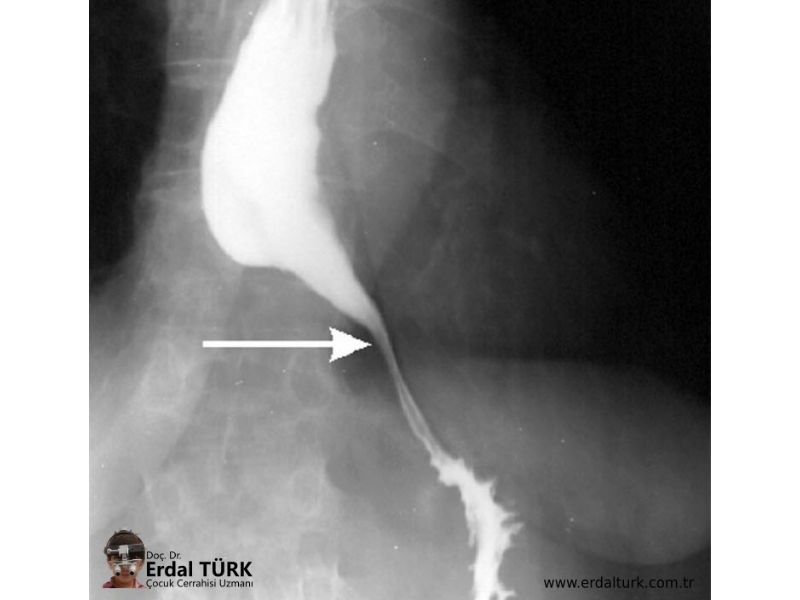

Кардиоспазм симптомы

Кардиоспазм симптомы 113 фотографий